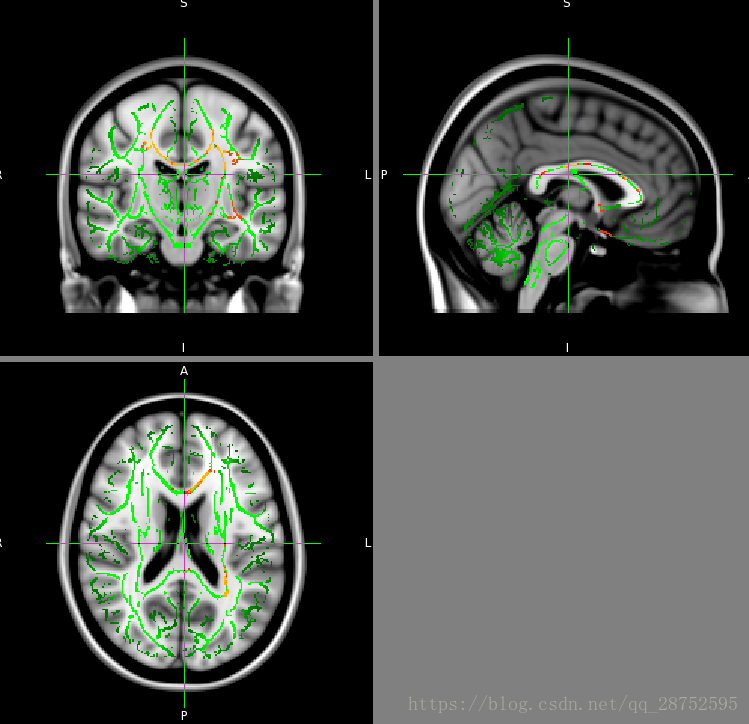

或者,尽管在TBSS骨架上显示统计结果是对所进行的实际分析的真实表示,但是如果骨架化结果在某种程度上“增厚”,则有些人发现更容易将结果可视化。为了简化这样的演示,有一个脚本tbss_fill,它会加厚阈值统计图像,将其填充到mean_FA中看到的本地“tracts”中。例如,要将此应用于上述相同示例,然后在mean_FA图像顶部的FSLView中查看,请运行:

tbss_fill tbss_tfce_corrp_tstat1 0.95 mean_FA tbss_fill fslview_deprecated mean_FA -b 0,0.6 mean_FA_skeleton -l Green -b 0.2,0.7 tbss_fill -l Red-Yellow